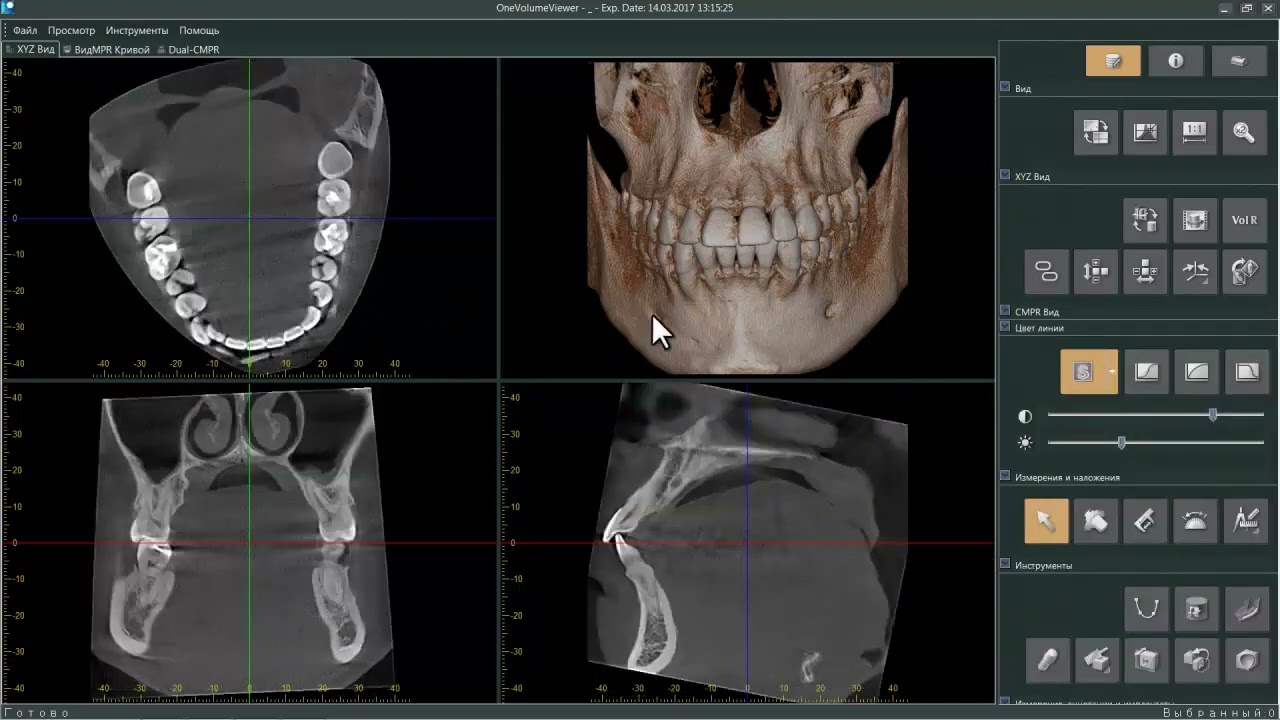

Как открывать кт файлы

Как открывать кт файлы 115 фото